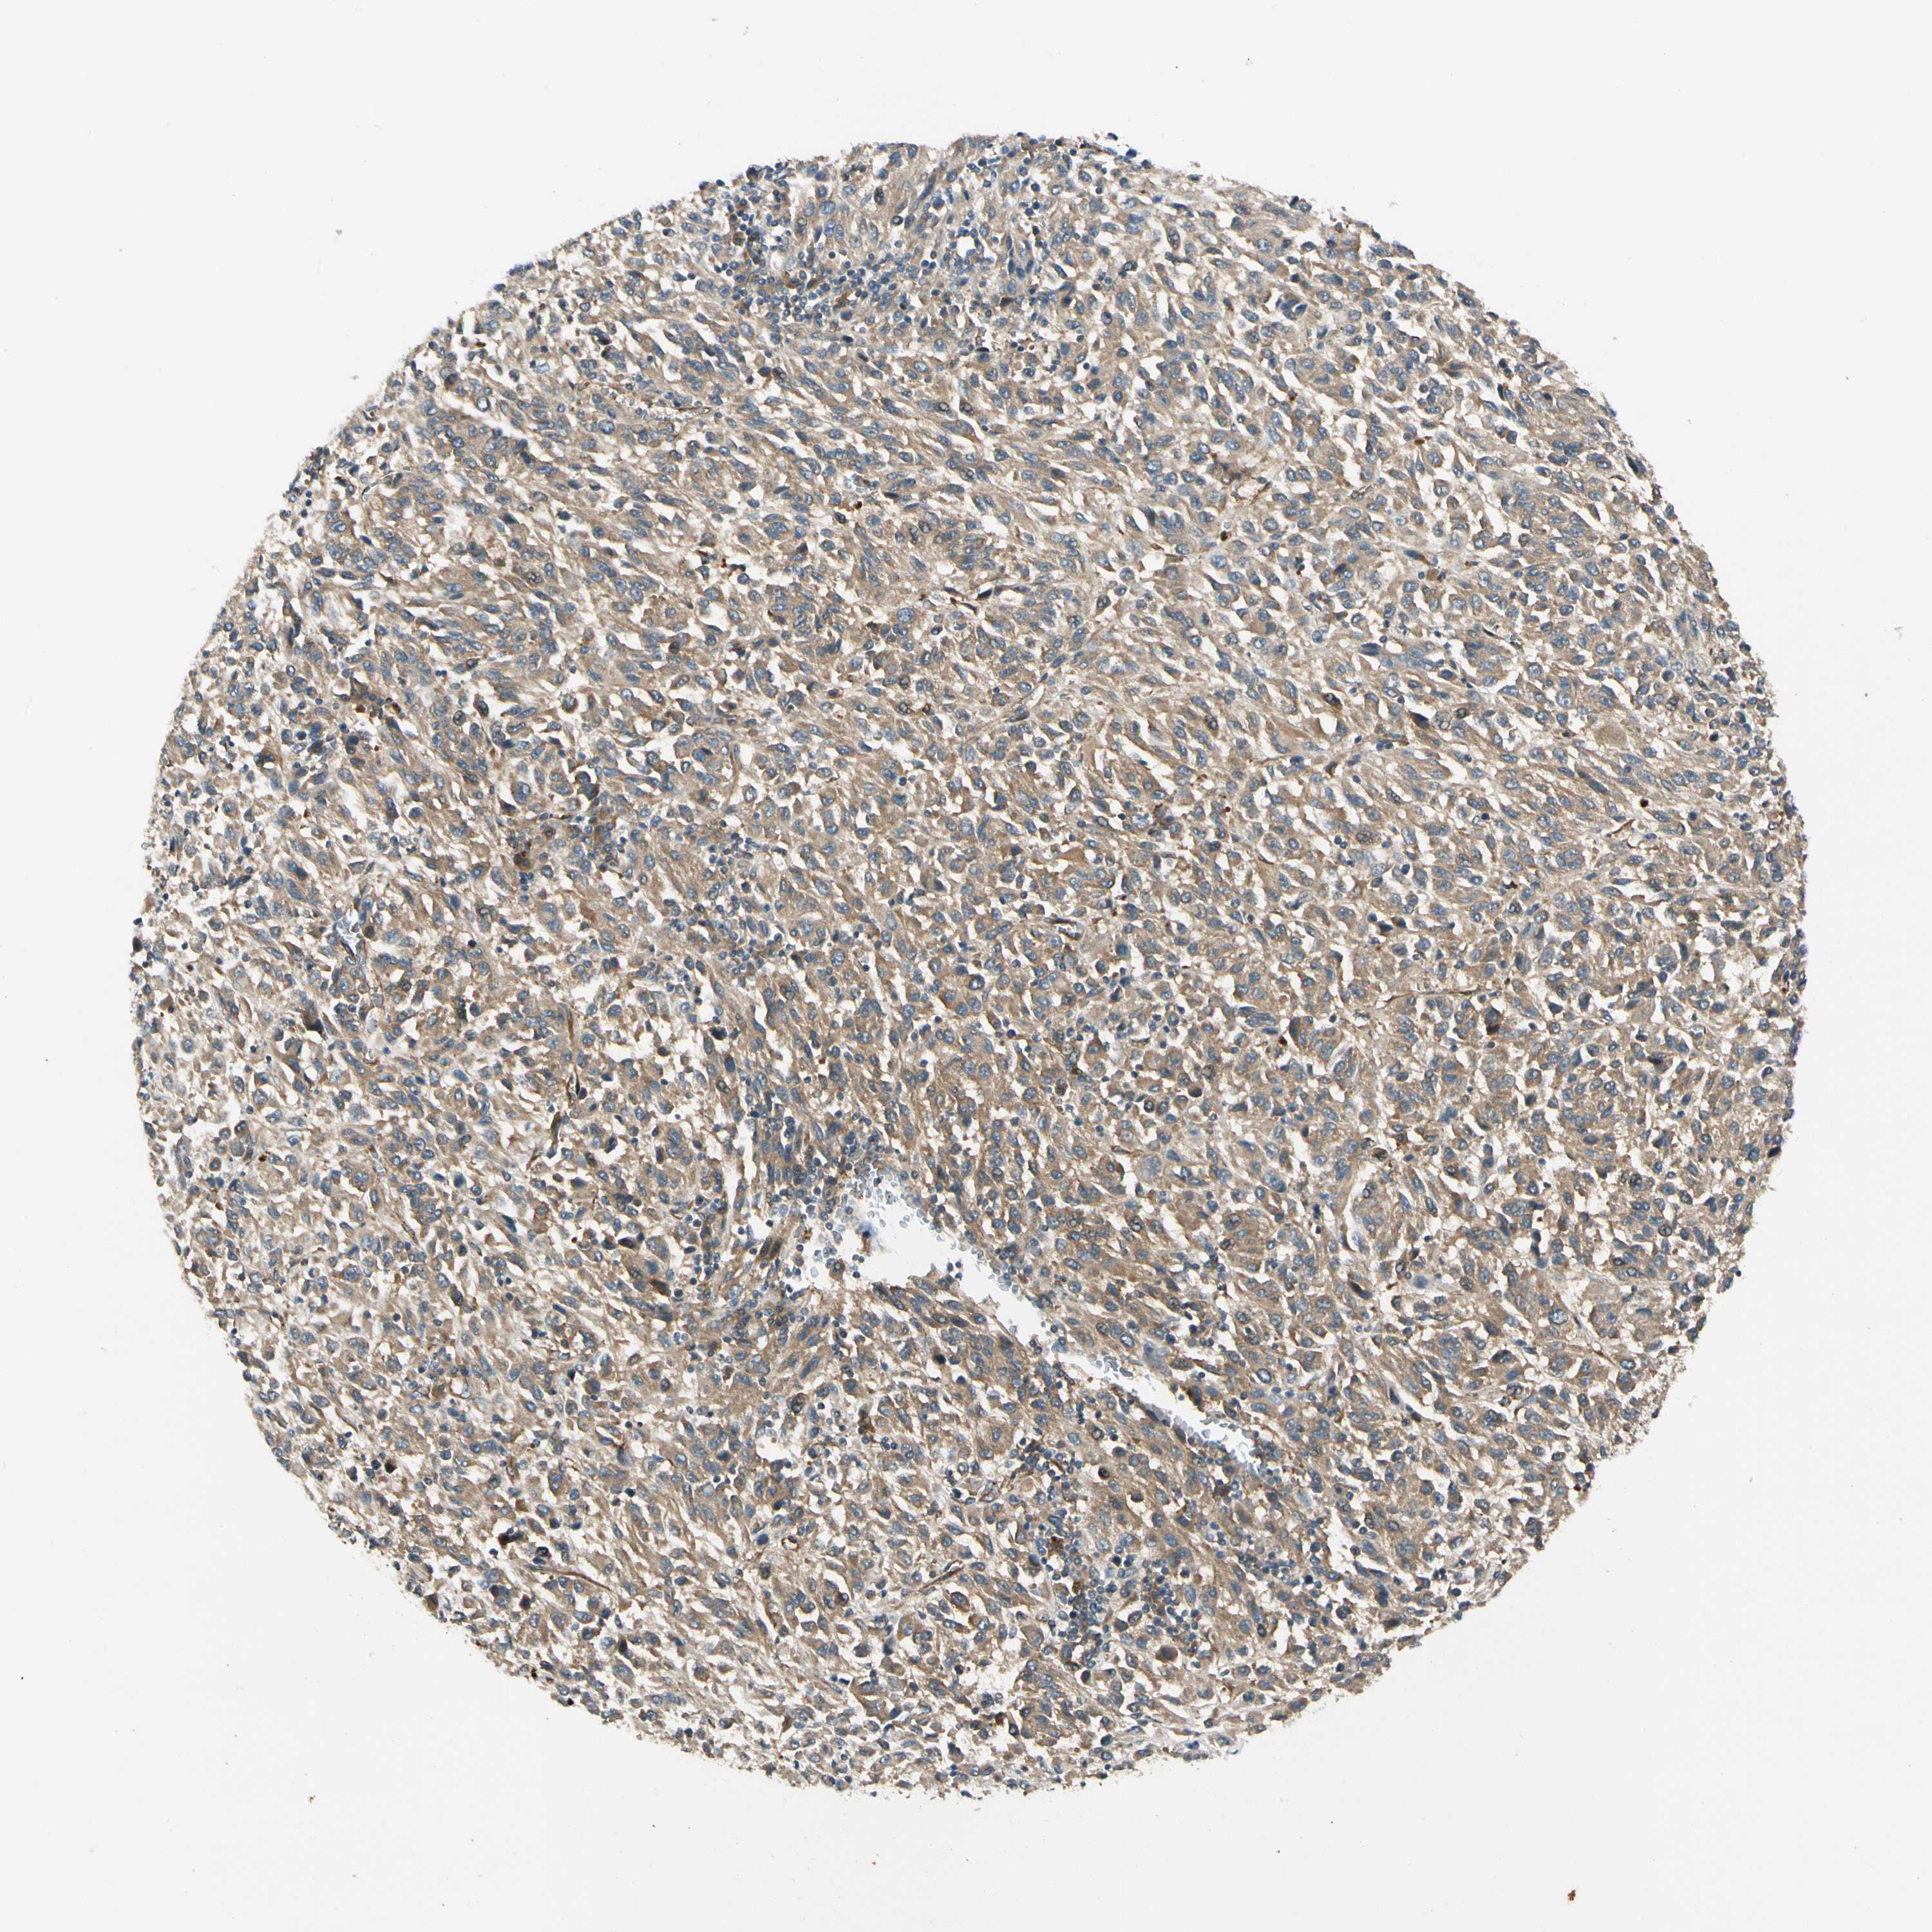

MELANOMA - Protein expressioni

A mouse-over function shows sample information and annotation data. Click on an image to view it in a full screen mode. Samples can be filtered based on level of antibody staining by selecting one or several of the following categories: high, medium, low and not detected. The assay and annotation is described here.

Note that samples used for immunohistochemistry by the Human Protein Atlas do not correspond to samples in the TCGA dataset.

Antibody stainingi

Antibody staining in the annotated cell types in the current human tissue is reported as not detected, low, medium, or high, based on conventional immunohistochemistry profiling in selected tissues. This score is based on the combination of the staining intensity and fraction of stained cells.

Each image is clickable and will lead to virtual microscopy that enables deeper exploration of all samples and also displays staining intensity scores, fraction scores and subcellular localization as well as patient and tissue information for each sample.

Antibody HPA007459

Antibody CAB008666

Staining

High

Medium

Low

Not detected

Intensity

Strong

Moderate

Weak

Negative

Quantity

>75%

75%-25%

<25%

None

Location

Nuclear

Cytoplasmic/membranous

Cytoplasmic/membranous,nuclear

Malignant melanoma, NOS

Malignant melanoma, Metastatic site